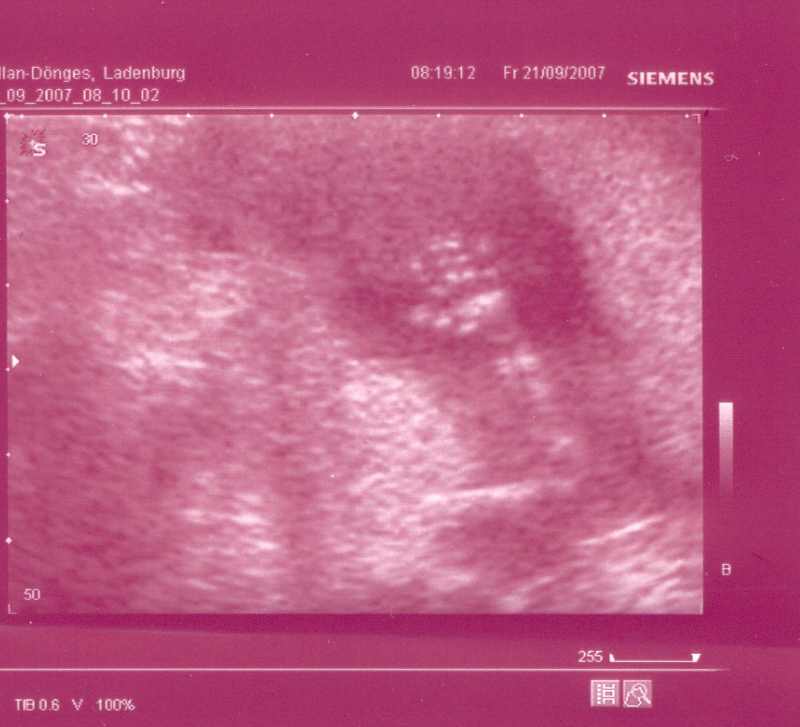

Naja endlich kam dann der US und zum Glück mit unserem Knödel ist alles OK ! Schön gewachsen auf 8,87cm und ganz eingekuschelt in meiner GM lag er/sie, da meinte meine FÄ dass Sie das Baby in dieser Lage leider nicht messen kann und SCHWUPS hat sich unser Knödel ganz genüsslich gestreckt und wir konnten schön messen.

Knödel  SSW 14+6.JPG

Ach so unser Knödel wollte euch auch mal winken

Knödelhand  SSW 14+6.JPG